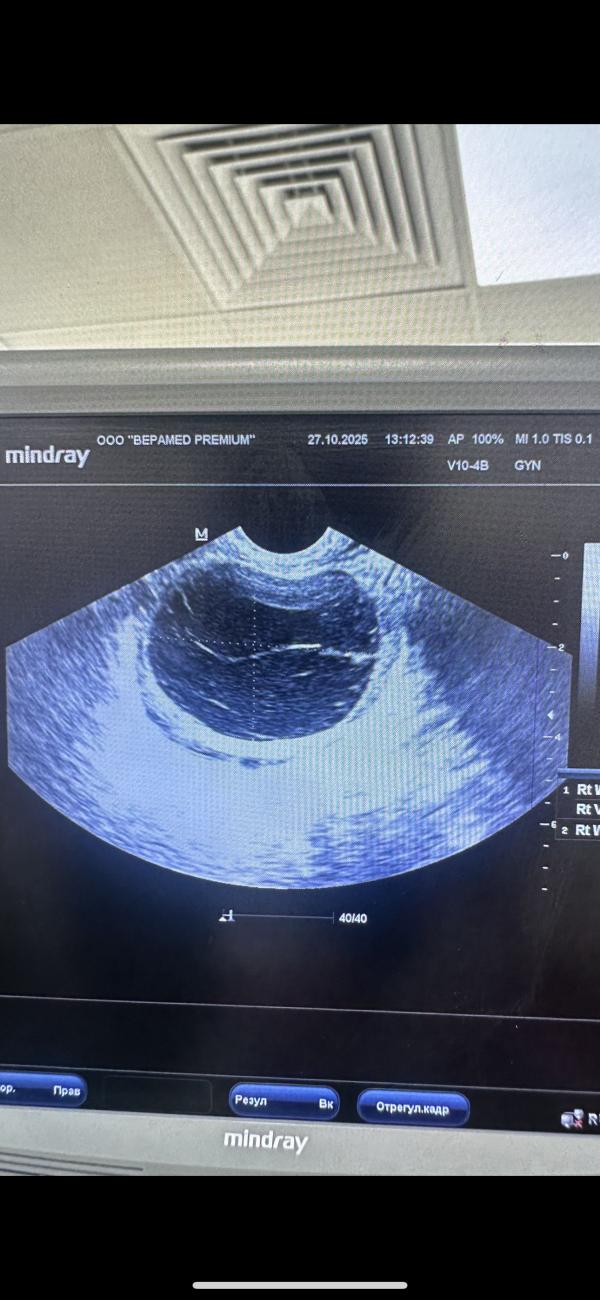

Фолликулярная киста и ХГЧ: что делать при отсутствии беременности

У меня фолликулярная киста, назначили хгч завтра уже наконец то